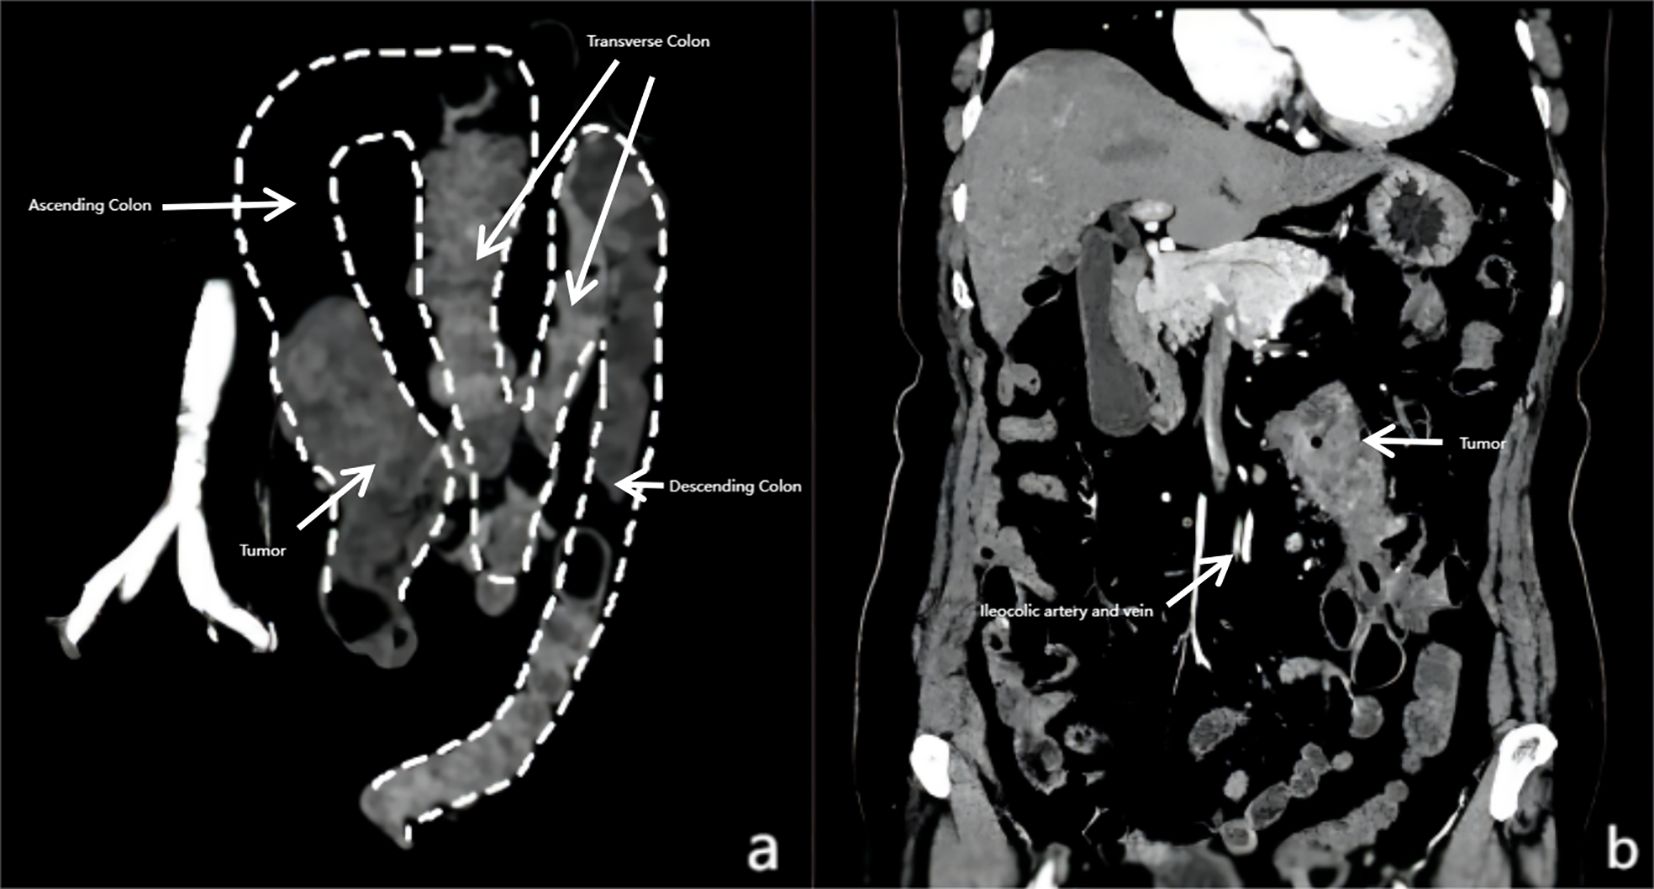

Intestinal malrotation (IM), a rare congenital anomaly, poses significant surgical challenges when coexisting with colorectal cancer—an association reported in fewer than 60 cases globally, predominantly in Japan. This study presents the first documented case in China of ascending colon cancer with nonrotation IM, successfully managed via laparoscopic right hemicolectomy with D2 lymphadenectomy. A 79-year-old female presented with abdominal pain, weight loss, and melena. Colonoscopy revealed an ascending colon mass, confirmed as adenocarcinoma. Preoperative contrast-enhanced CT demonstrated left-sided colonic malposition, an "M"-shaped colon, and anomalous ileocolic vasculature originating from the left of the superior mesenteric artery. A multidisciplinary team employed meticulous preoperative planning, utilizing multiplanar CT reconstruction to navigate anatomical complexity. Laparoscopic surgery involved adhesiolysis, division of Ladd’s bands, and D2 dissection, achieving R0 resection (pT3N0M0) with 50 mL blood loss and no intraoperative complications. The patient recovered uneventfully, discharged on postoperative day 9, with no recurrence at 18-month follow-up. This case underscores the feasibility of minimally invasive techniques in IM-associated malignancies when guided by embryological insight and advanced imaging. Key technical strategies included adaptive port placement, stepwise anatomical correction, and vascular tracing to ensure oncological adequacy. The successful integration of laparoscopic principles with anomaly-specific modifications highlights a paradigm for managing such rare presentations. Our findings emphasize that IM’s anatomical complexities need not preclude laparoscopic benefits, advocating for global case-sharing to refine standardized protocols and expand minimally invasive options in complex surgical oncology.